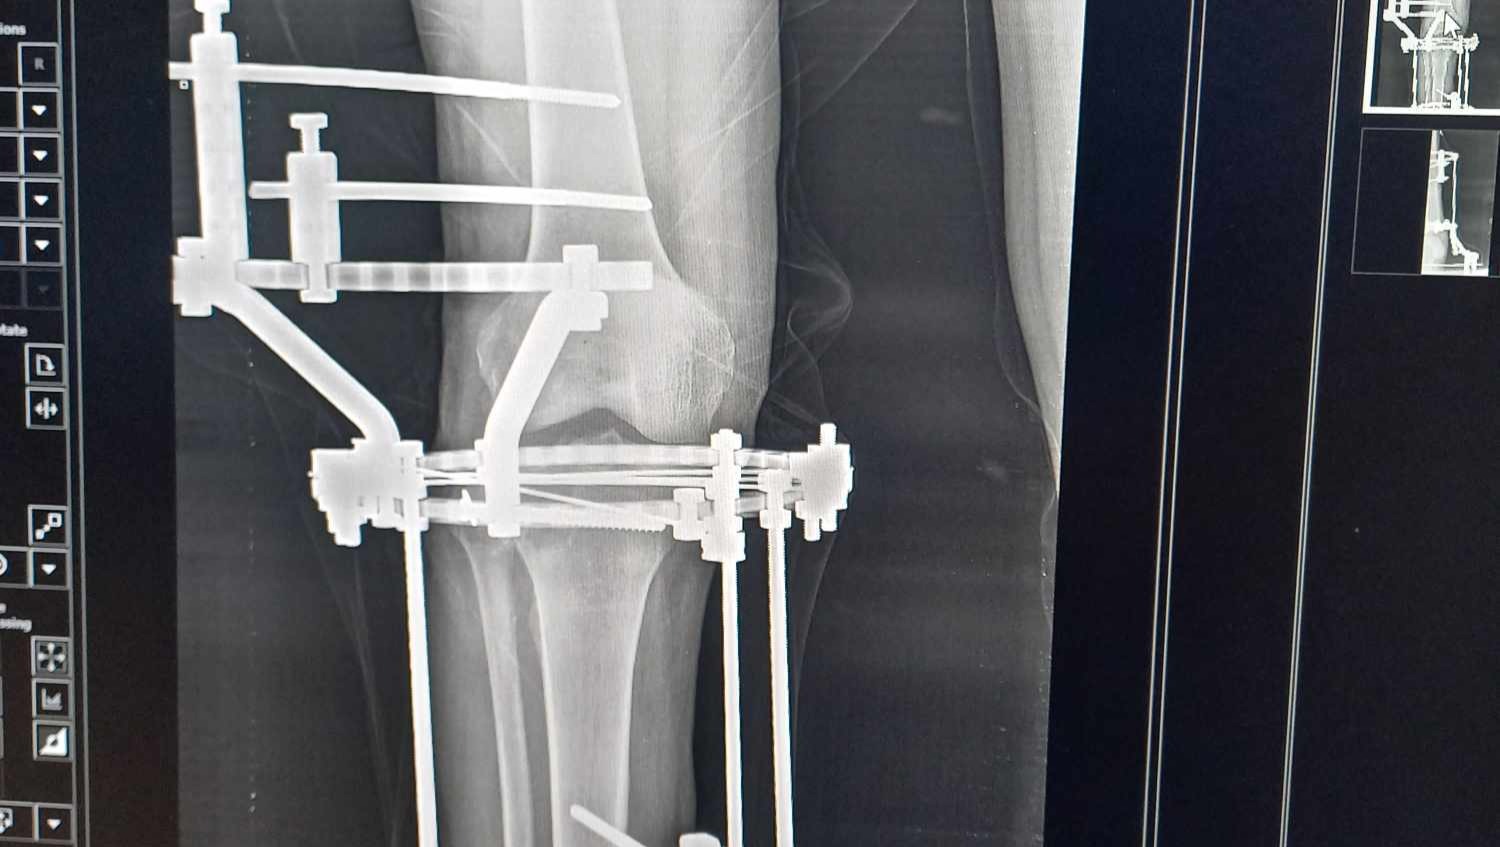

In March of last year, our world turned upside down when my dad had a bad motorcycle accident. The crash broke his knee and shoulder bones really badly, and he needed surgery with a special metal plate to fix them. He had one surgery, but it wasn't enough to make him feel completely better again. And on top of all that, his shoulder was broken again during the war. His health plummeted, and he found himself right back where he started.